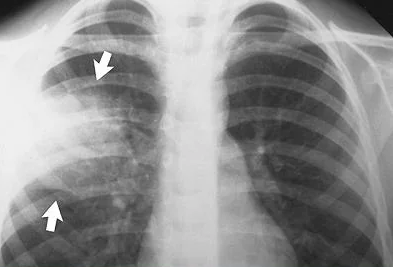

¿Qué nos permite ver la radiografía?

A

• Columna de aire tráquea

• Ángulos borrados

• Consolidaciones o patrón intersticial